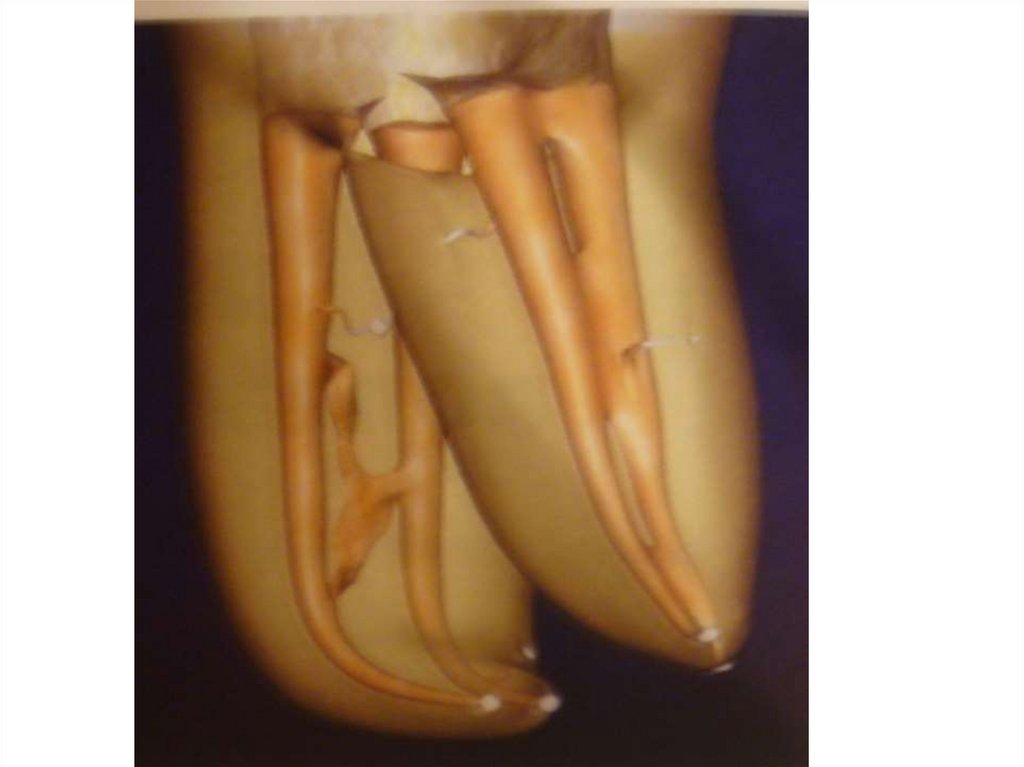

48. Пломбирование МВ2

49. 7- канальный п.в.моляр 16